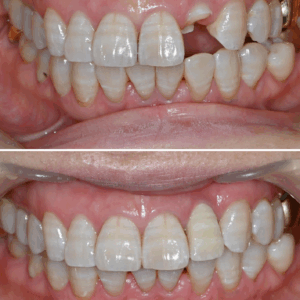

울산달동하나치과 벌어져 있는 앞니 라미네이트 수복

울산달동하나치과 벌어져 있는 앞니 라미네이트 수복   안녕하세요! 하나치과입니다~:) ​ 앞니는 웃을 때 가장 많이 보이는 부분으로 사람의 인상을 구분 짓는 만큼 얼굴에서 중요한 부분을 차지합니다. ​ 앞니가 벌어지게 되면 미관상으로도 좋지 않을 뿐만 아니라 음식물이 그 주변으로 끼면서 충치나 잇몸질환이 발생하는 2차적인 문제가 생길 수 있는데요. ​ 이처럼 벌어진 더보기…